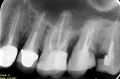

Лет 10 назад откололся кусок зуба, нерв не удаляли, поставили пломбу. Получилось, что половина зуба своего, половина пломба. Около года назад стало на этой стороне неудобно кушать — что то твердое попадало на зуб, потом все более и более это стало ощущаться. И вот недавно сверху откололся кусочек зуба, потом его стенка. Картина такая: стоит пломба, и половина зуба, от той половины. Я боюсь что остаток зуба держит именно пломба. Какие варианты лечения возможны? Какие последствия?

Сегодня, как и в прошлый раз, необходимо установить культевую вкладку, а затем и коронку. А последствия могут быть печальными, если зуб скоблится ниже десны, то к сожалению, зуб придется удалить. Не теряйте время и срочно к врачу.